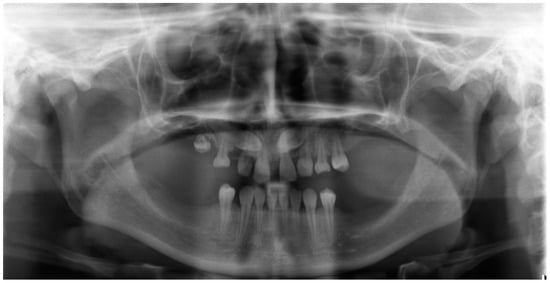

| May–August 2022 | Finishing; control panoramic X-ray (Figure 8); 1st canine relationships and midline consistency; debonding of the brackets; fixed upper and lower retainers’ placement (0.027″ × 0.011″ 8-strand braided SS), tooth no. 24 was not fixed to the retainer due to increased mobility. |

| September 2022 | E-max (lithium desilicated ceramic) veneers on upper teeth; individual implant abutments (titanium pre-milled abutments) and implant-supported blocked crowns (zirconia veneered with porcelain using the cut-back technique) on dental implants; removable thermoformable retainer. |

| March 2023 | Retention phase: 10-month follow-up. Stability of treatment results; minimal opening of the spaces mesially to teeth no. 34 and 44; proper mobility of tooth no. 24. Bleaching of the lower teeth. |